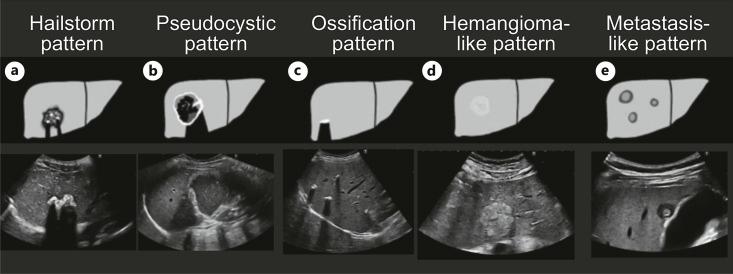

The use of the ultrasound classification developed by us and the use of contrast-enhanced ultrasound (CEUS) helps make the diagnosis faster and better. Without CEUS, the hemangioma-like pattern and the metastasis-like pattern in particular cannot be diagnosed with certainty. The limitations of ultrasound diagnostics on the patient side, in terms of examiner experience and equipment, remain.

使用我们开发的超声分类方法以及对比增强超声(CEUS)有助于更快、更好地进行诊断。没有CEUS,特别是血管瘤样模式和转移样模式无法确诊。在患者方面,超声诊断在检查者经验和设备方面的局限性仍然存在。